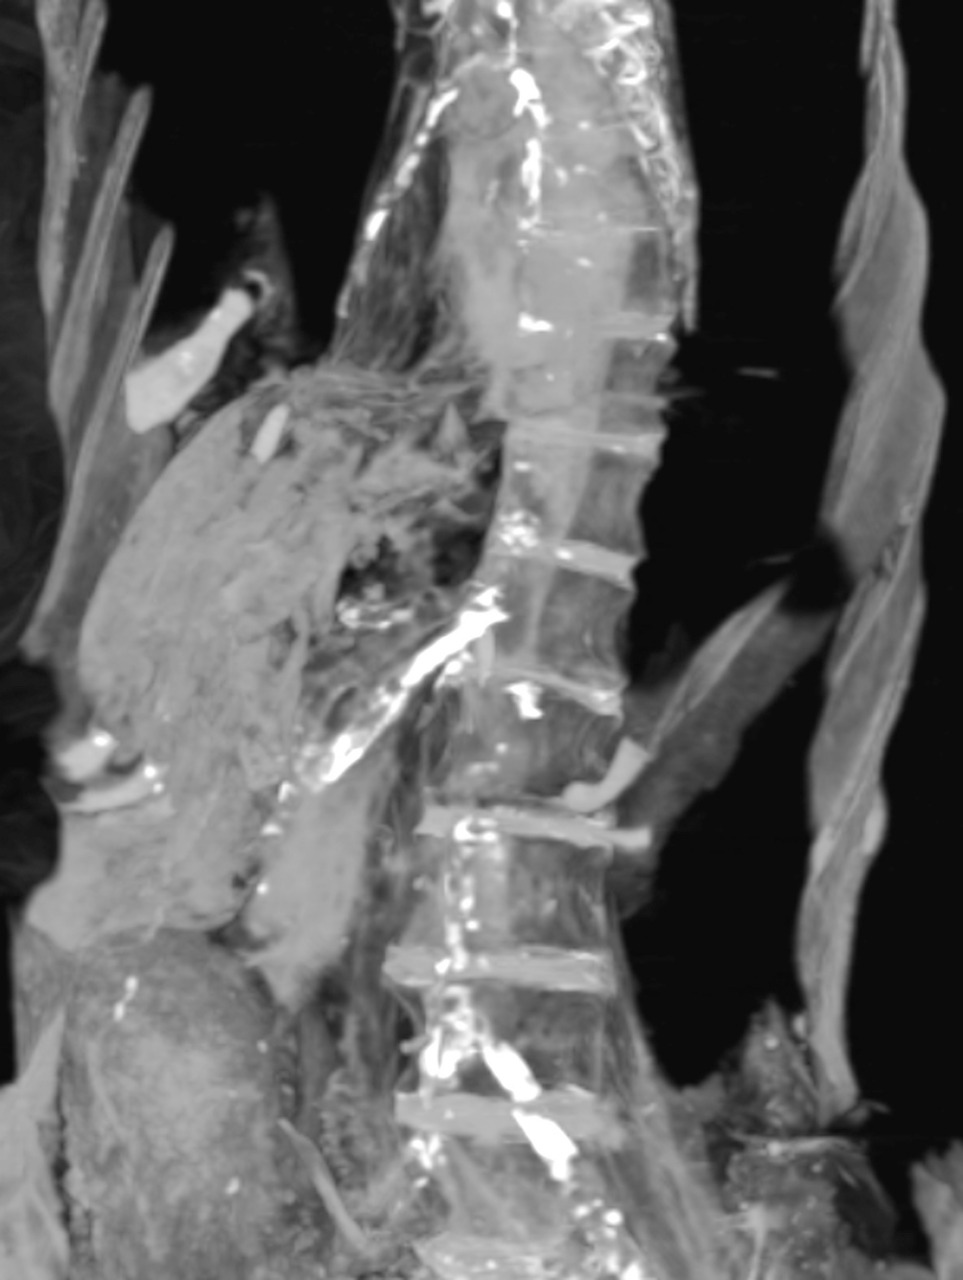

The results showed that the woman died in her 50s and that she received good mummification treatment. The results also showed that she suffered from atherosclerosis of the right and left coronary arteries, neck arteries, abdominal aorta and iliac arteries, as well as the arteries of the lower extremities.

The team believes that the woman had a massive heart infarction resulting in her sudden death. Consequent to death, her head was tilted to the right side and her jaw dropped. The dead body must have been discovered hours later, enough to develop death spasm. Stiffening of muscles and joints following death is termed death spasm (rigor mortis) which starts a few minutes to several hours after death.